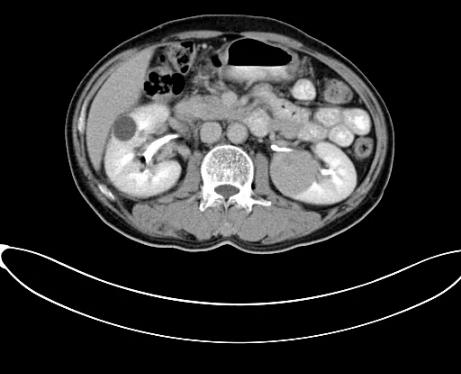

據安圖叔叔的兒子回憶道,安圖叔叔在體檢前沒有發現任何不適的癥狀,在體檢后才知雙腎占位,右腎下級占位16.1*7.2cm,左腎下級腫瘤約3.7*4.3cm的情況。突如其來的病情讓一家人陷入了恐慌,從未想過一個健康自律的人會突然間就被檢出腎癌,還是雙腎。安圖叔叔的兒子激動地說道:“我當時一下子懵了,父親之前表現那么健康,一查竟病得很重,為確診我把父親轉接到新加坡就診,那邊的醫生在看了我父親的片子后都表示這是腫瘤,要做切除雙腎然后再透析,對于我們來說,切腎這樣的治療方案對我們來說是無法接受的,父親畢竟一把年紀,這樣做法太傷他身體。”

2017年9月安圖叔叔開啟新治療之路,入院檢查發現安圖叔叔右腎透明細胞癌T3NxM1IV期、左腎癌、縱隔淋巴結轉移瘤。為緩解安圖叔叔腰疼的狀況,9月21日進行介入治療。經復大專家認真探討后,考慮到安圖叔叔身體精神狀態良好,可進行冷凍消融術。經專家解說和安慰后,安圖一家懸著心終于放下了。

2017年9月29日,從CT影像看到右腎情況更為嚴重。為減緩腫瘤增長的速度,專家進行商議后,最終決定由牛立志教授主刀為安圖叔叔進行了右腎腫瘤冷凍消融術。手術開始后,牛立志教授在CT和超聲引導下,同時使用兩根冷凍針固定病灶,精準滅活腫瘤;術后很成功無不良反應。術后一周進行第二次雙腎腫瘤冷凍消融術。安圖叔叔兒子笑道:“當時真的很緊張,醫生勸慰我無須擔心,都交給他們,我們都很清楚知道父親的病情,真的很感謝也很慶幸我父親遇到復大的醫護人員,免受開刀之痛。住院期間醫護人員很盡心盡力的照顧父親,手術的成功離不開他們的辛勞付出。”

隨著時間的推移,安圖叔叔身體開始發生明顯變化,腰疼的癥狀得到緩解,血尿的次數明顯減少,睡眠質量有明顯的改善。以前上廁所都是一件很痛苦事情,如今逐漸正常。安圖叔叔的病情得到改善,在一次次的復查中得到主治醫生王峰的佐證。過去的兩年里,安圖叔叔一直遵循醫生的囑咐,按時服藥定時回院復查,到目前為止是安圖叔叔第9次來院復查。安圖叔叔的兒子說道:“我每次帶父親來檢查都有新發現,腫瘤在一天天的變小,我們很相信醫生的話,他們會給我們最好的治療方案,如今已過去兩年,父親身體和精神慢慢轉好,這是我們所希望的。”